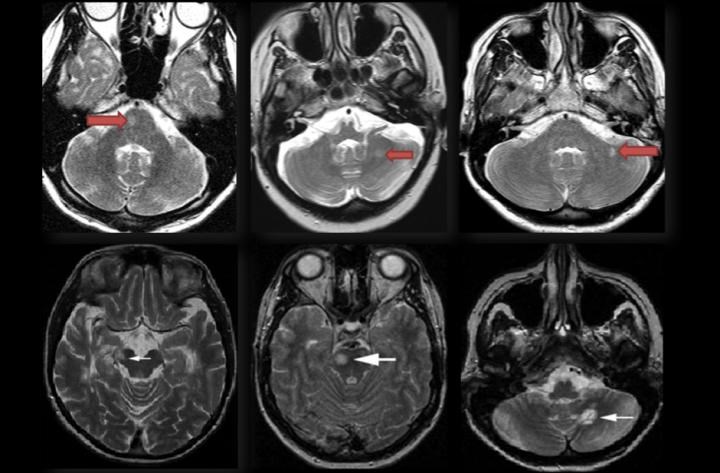

Tipik lezyon lokalizasyonları

- Korpus kallozum lezyonları

- Periventriküler lezyonlar

- Beyin sapı / infratentoriyal lezyonlar

- Jukstakortikal lezyonlar

- Spinal kord lezyonları

Bu bölgelerdeki örnek lezyon alanları, MRG üzerinde İMG – MRG-1’den İMG – MRG-6’ya kadar olan görsellerde gösterilmiştir.

İMG – MRG-1: Tipik T2 lezyonları.

İMG – MRG-2: Korpus kallozum ve periventriküler lezyonlar.

İMG – MRG-3: Beyin sapı / infratentoriyal yerleşim.

İMG – MRG-4: Periventriküler yerleşimli lezyonlar.